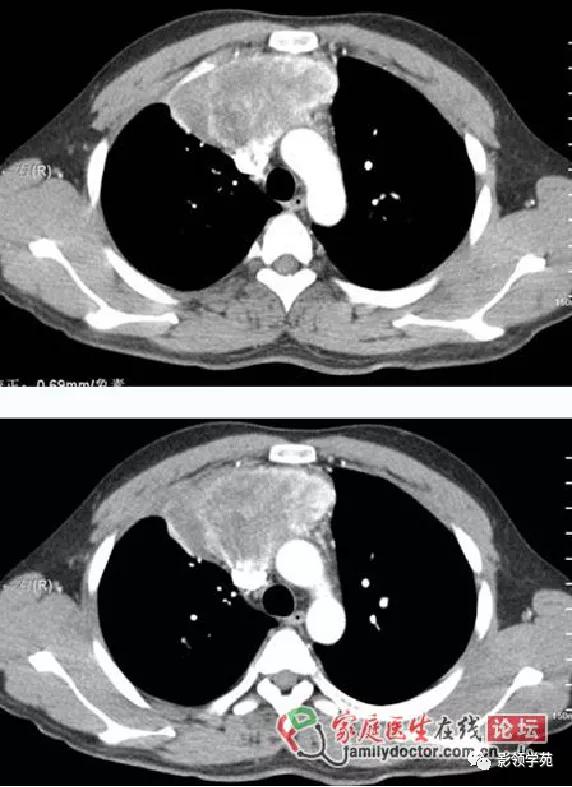

淋巴结肿大融合,压迫上腔静脉,致上腔静脉狭窄

淋巴结肿大融合,轻度强化,与血管形成鲜明对比

融合呈团的淋巴结中央见片状坏死